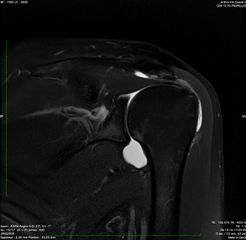

Magnetic resonance arthrography (MRA) of a left subacromial impingement. Note the important compression done by the acromion and the coracoacromial ligament on the supraspinatus tendon.